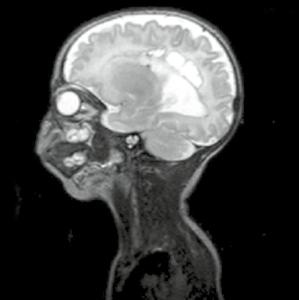

Kazuistika

Chlapec, stáří 14 dnů, protrahovaný porod, kříšen, po porodu hypertonický, křeče, poruchy vědomí.

Obr. A3.1–A3.4 „Super scan“ – kombinace periferního a centrálního typu postižení, s krvácením. Šipka v obr. A3.1 – centrální léze, šipka v obr. A3.3 – drobná krvácení, šipka v obr. A3.4 – periferní léze A3.1